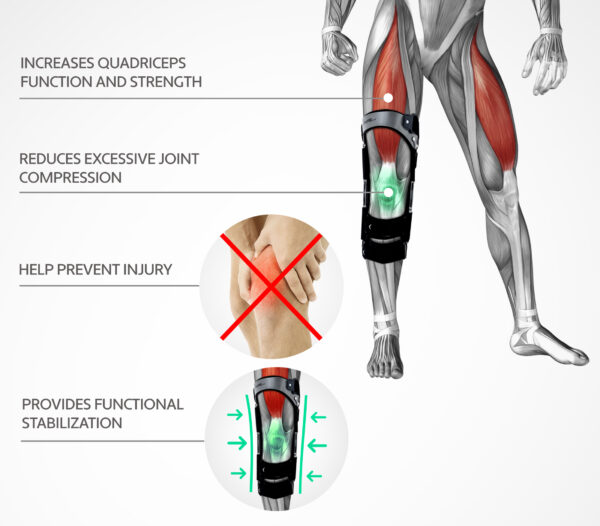

RAPTOR BIONIC is more than ordinary knee brace. It has innovative bionic construction, because of spring loaded hinges. It stores energy when the user flexes the knee (while placing weight on the legs) and releases energy when the user extends the legs. While knee extending, the stored forces support the knee extensors.

In result, the brace stabilizes the joint, and increases the knee’s strength and power.

Researchers have focused on ligaments with survey device supported by braces and they noticed significant decreasing of ligament’s tension (in standing and sitting position) in compare to unsupported leg. Effectiveness of this kind of support is undeniable. The 4 Points braces protect knee joints against the injury during sport and everyday activities. They minimalize the risk of additional soft tissue injuries before surgery. In postoperative period they provide protection of ligaments insertion for remodeling time (about 12-18 months). During rehabilitation the 4 Points braces allow for more “aggressive treatment” by mobilizing the ligament and other soft tissue to healing.

Researches claim that the 4 Points braces help to protect ACL against the stretching and both during the load and not, the 4 Points braces have decreased ACL tension. It is result of reaction against the forward forces. For example: in case of loading, the orthoses have decreased the ligament tension of 50%.

The most important advantages of using orthopaedic knee braces with 4P technology is that:

1. They decrease ACL tension what is very important during ligament remodeling.

2. They compress the time of being in submaximal extension or in “dangerous” position

3. They increase the force on the tibia aback to prevent its shift (drawer syndrome)

4. They eliminate extension shock in the last phase of knee extension in patients with raptured ACL (100% ACL rapture prevention!)

Undoubtedly, the above evidence prove ACL tension reduction properties of 4P RAPTOR BIONIC during the rehabilitation and remodeling process. Thanks to using this brace a patient achieves reduction of ligament’s weakness as well. RAPTOR BIONIC is the best protection of knee ligaments. It provides maximum safety and knee protection so it is created for athletes especially.